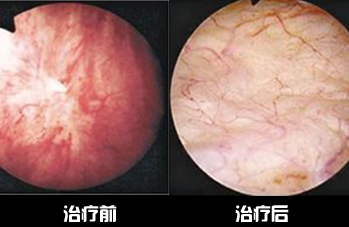

膀胱炎